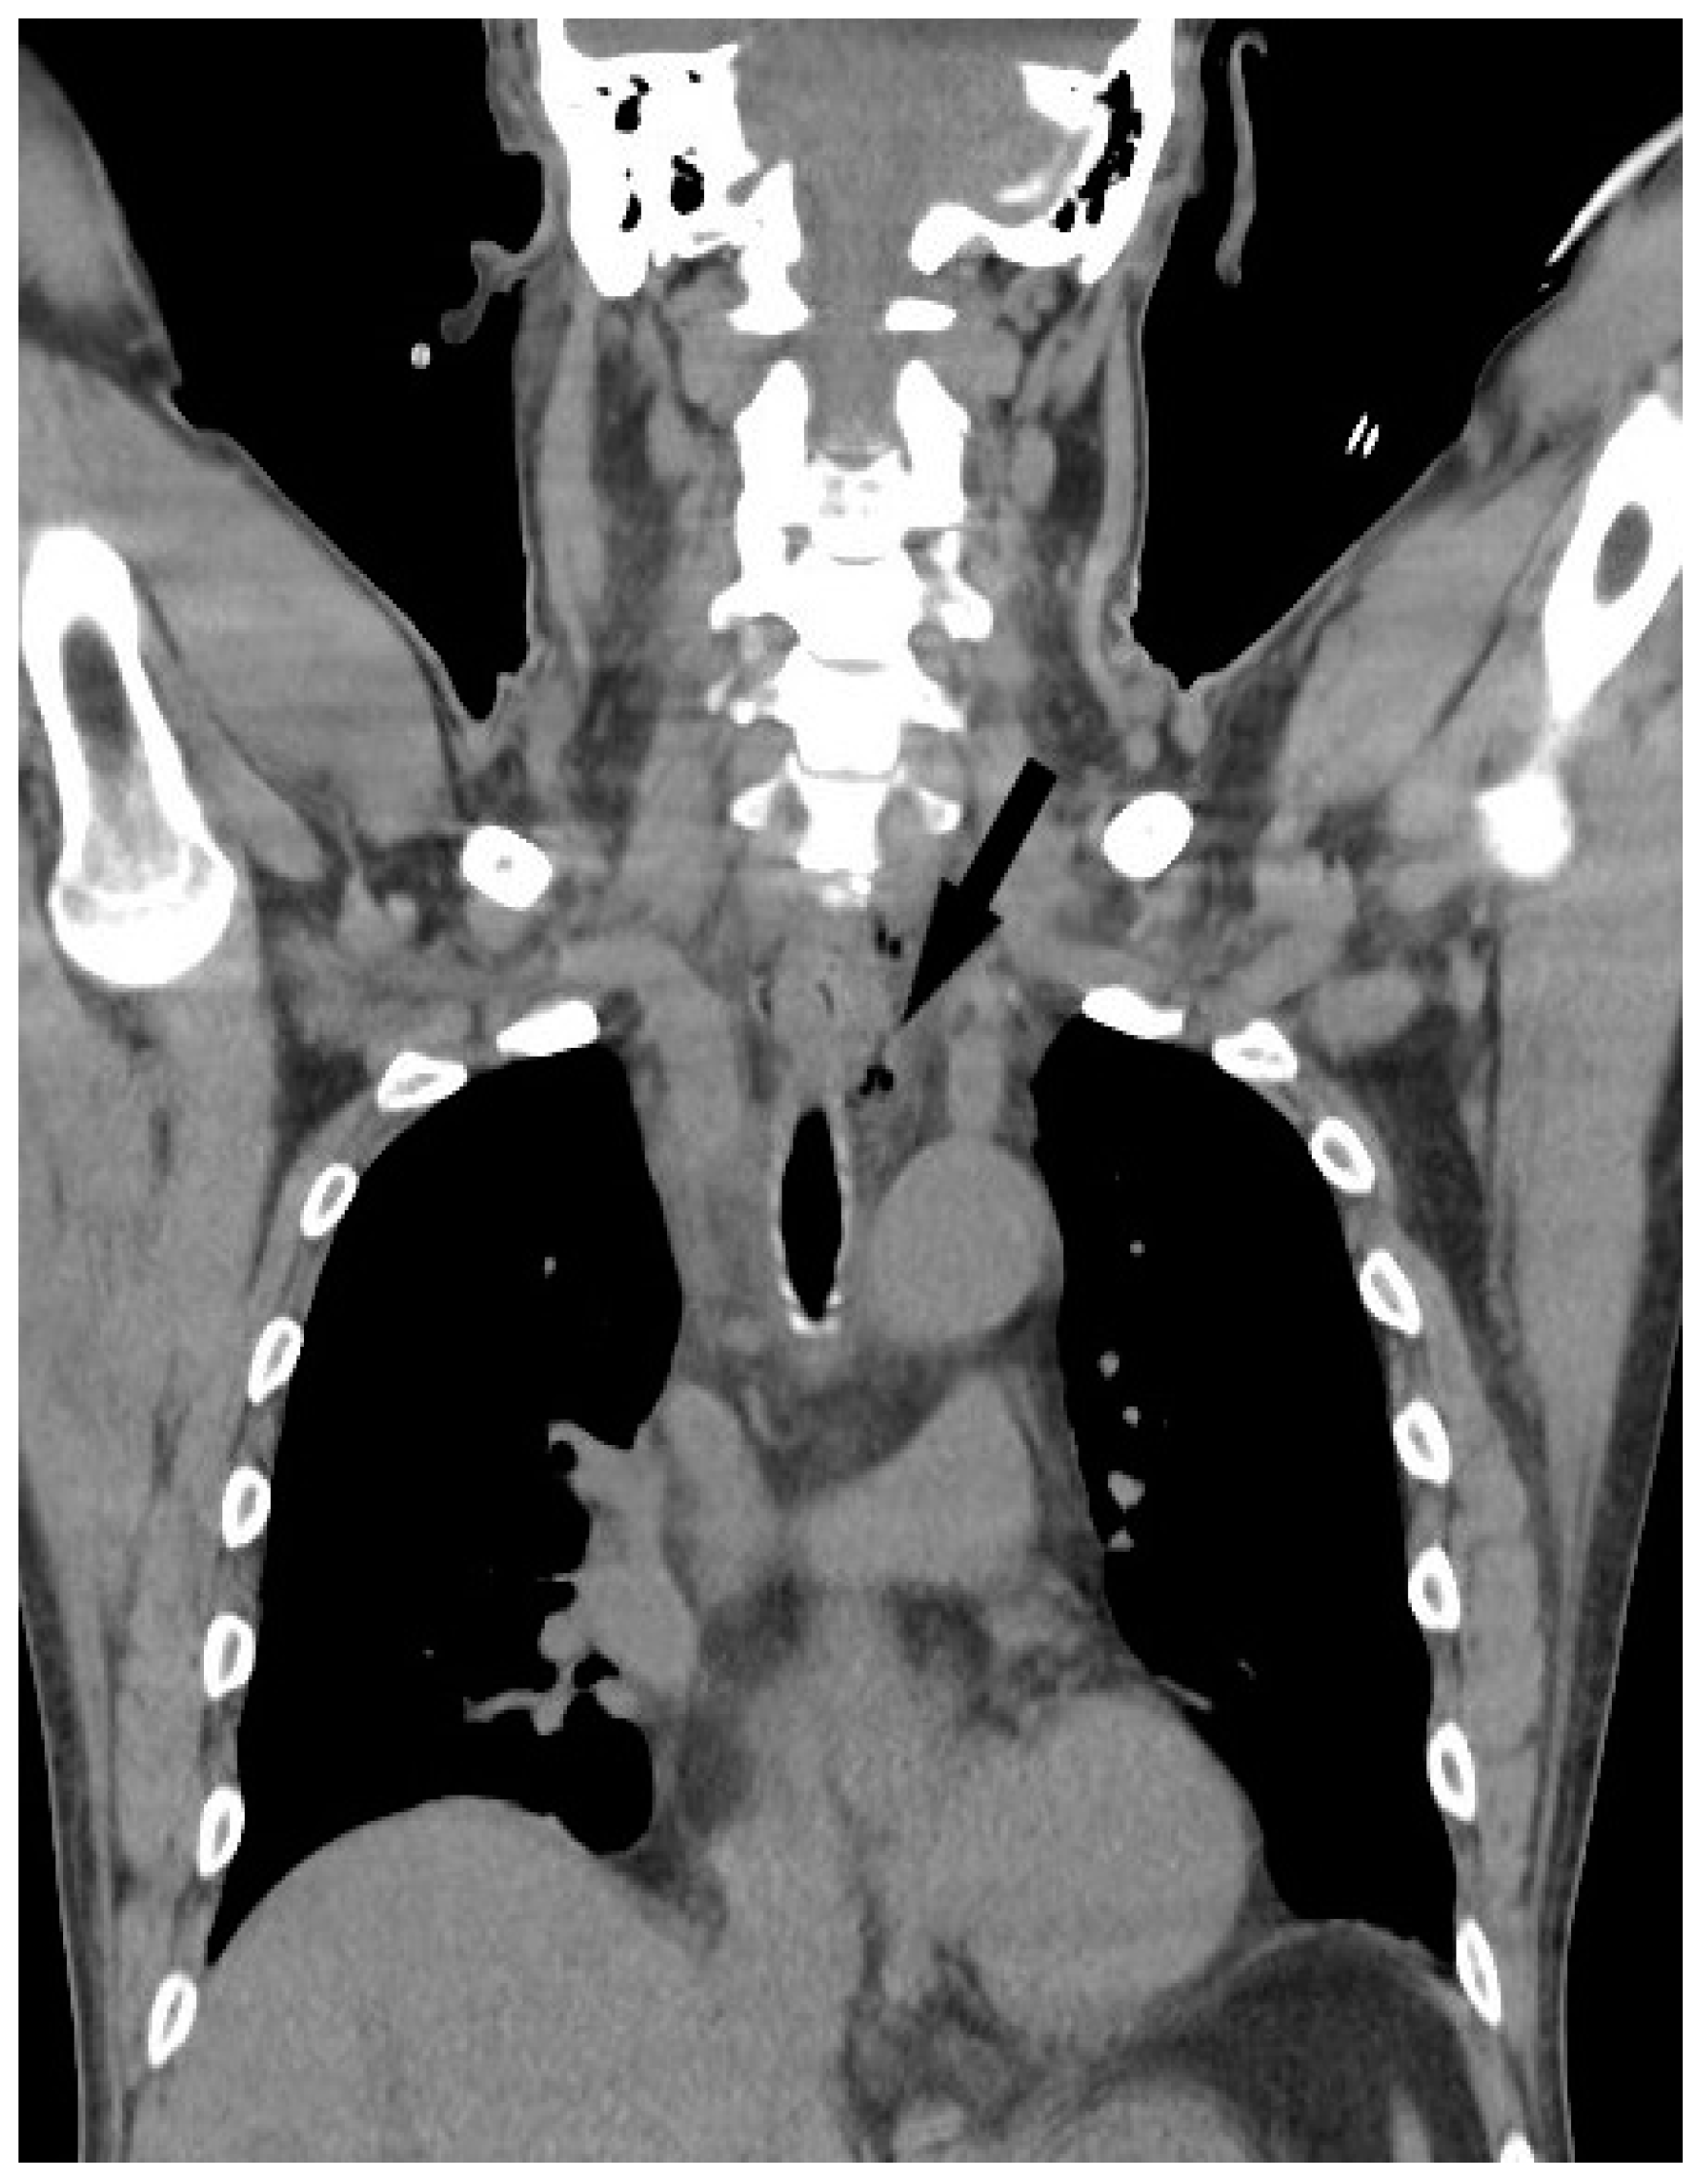

The study was approved by the institutional review board of Chang Gung Memorial Hospital (approval no.202201372B0). We retrospectively reviewed the medical records of patients undergoing surgical treatment of deep neck abscesses from August 2017 to July 2022. Computed tomography (CT) was performed in all patients. Submandibular abscesses are those that extend from the mouth floor to the mandible bilaterally (Figure 1a). Submental abscesses affect the central neck from the floor of the oral cavity to the hyoid bone (Figure 1b). Masticator abscesses extend cranio-caudally between the skull base and mandibular ramus, and transversely between the medial pterygoid and masseter muscles. Parotid abscesses are defined by the presence of pus in and around the parotid gland. The parapharyngeal space contains predominantly fat and is a cone-shaped space from the skull base to the hyoid bone. The peritonsillar space is above the parapharyngeal space and around the bilateral tonsil. Retropharyngeal abscesses are located between the pharynx and vertebra, extending from the skull base to the level of the T2 thoracic vertebra. The anterior visceral space, also called the pretracheal space, lies between the infrahyoid strap muscles and esophagus. DNM can be confirmed on chest CT (Figure 2) and culture from mediastinal fluid drained during surgical intervention. All patients with a deep neck abscess were treated with empiric intravenous antibiotics (Ceftriaxone 1 g Q12H and Clindamycin 500 mg Q8H). Antibiotic treatment was then adjusted based on bacterial culture and sensitivity test. After surgical drainage of the deep neck abscess, the neck wound was irrigated with povidone iodine solution 2–3 times per day according to the wound condition. Thoracotomy was performed in patients with DNM of the anterior inferior and posterior mediastinum. Tracheostomy is not routinely performed in these patients. Tracheostomy is performed in patients with respiratory distress and dependent on endotracheal tube for more than two weeks. Exclusion criteria included patients with neck cellulitis without abscess formation, patients with necrotizing lymphadenitis due to lymph node metastasis, and those without CT images to evaluate the extent of the abscess. Before surgery, lab data including hemoglobulin (Hb), white blood cell count, neutrophil percentage, C-reactive protein (CRP) level, and blood glucose were recorded. Patients’ characteristics including gender, age, etiology, and presenting symptoms were collected. Hospitalization duration and bacterial cultures from the wound were also analyzed. Fisher’s exact test was used to compare nonparametric variables including sex, symptoms at presentation and location of the abscess. Mann-Whitney U test was used to analyze parametric data (age, Hb, WBC, CRP, etc.). The data were analyzed using SPSS for Windows, version 20.0. Statistical significance was defined as p < 0.05.

Figure 2.

Air-containing abscess (black arrow) extends from deep neck space to the upper mediastinum.